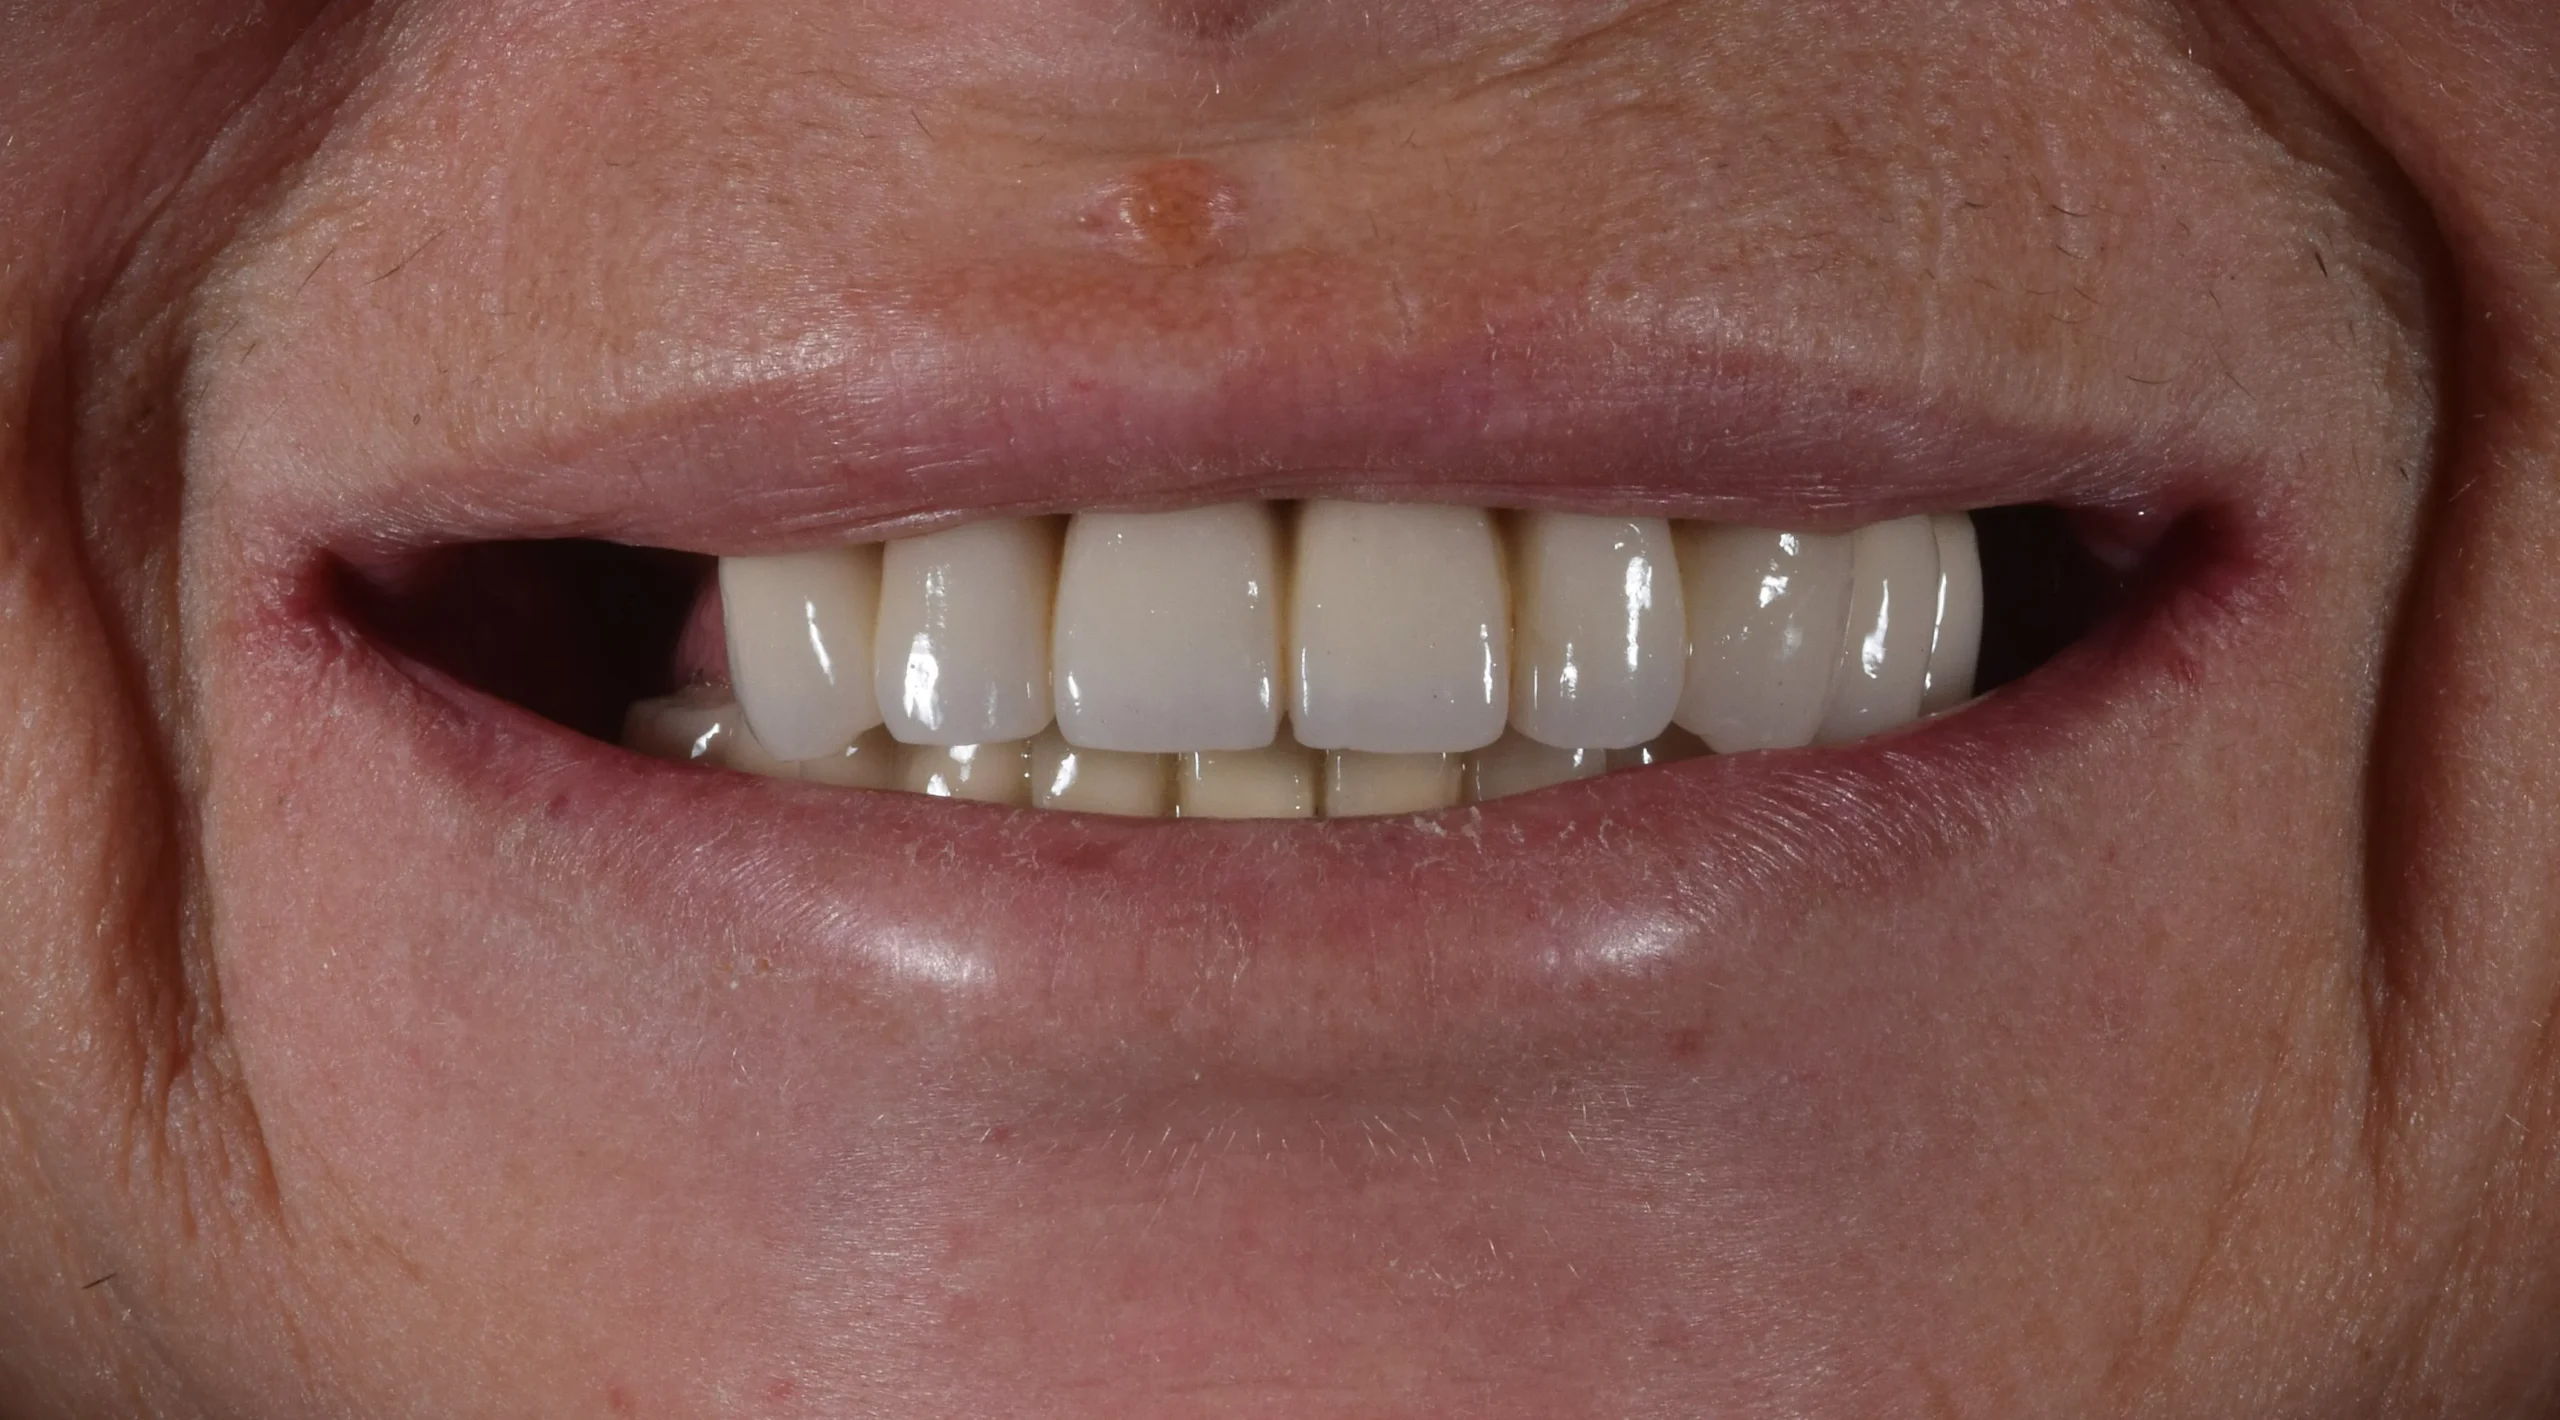

The vertical dimension of the occlusion was raised, so not only did we get a new smile, but the results showed up on the patient’s skin, achieving a younger and more fresh look.

The digital workflow allowed us to achieve this beautifull result. We strive to use all the available tools to achieve predictable results like this.